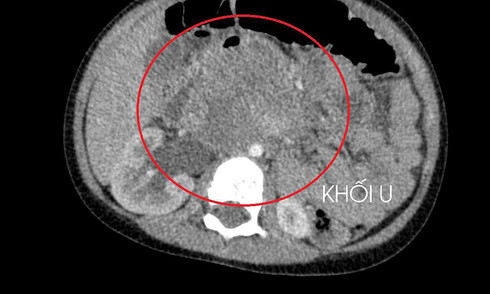

A young boy frequently experienced periumbilical abdominal pain, leading doctors to discover a large tumor compressing his kidney, a result of metastatic testicular cancer.